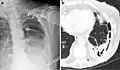

Extensive left-sided fibrothorax

Chest radiograph displaying inhomogeneous opacification of the left half of the chest that is fibrothorax

A fibrothorax can typically be diagnosed by taking an appropriate medical history in combination with the use of appropriate imaging techniques such as a plain chest X-ray or CT scan.[3] These imaging techniques can detect fibrothorax and pleural thickening that surround the lungs.[7] The presence of a thickened peel with or without calcification are common features of fibrothorax when imaged.[3] CT scans can more readily differentiate whether pleural thickening is due to extra fat deposition or true pleural thickening than X-rays.[3]

If a fibrothorax is severe, the thickening may restrict the lung on the affected side causing a loss of lung volume.[7] Additionally, the mediastinum may be physically shifted toward the affected side.[3] A reduction in the size of one side of the chest (hemithorax) on an X-ray or CT scan of the chest suggests chronic scarring.[6] Signs of the underlying disease causing the fibrothorax are also occasionally seen on the X-ray.[6] A CT scan may show features similar to those seen on a plain X-ray.[7] Lung function testing typically demonstrates findings consistent with restrictive lung disease.[6]